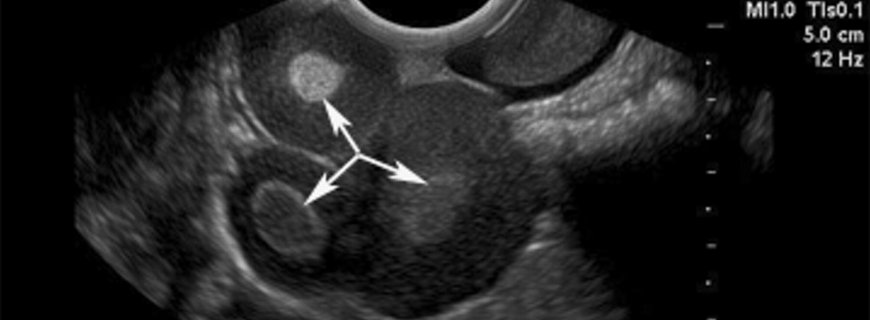

Seröz kistadenoma için kullanılan benzer tespit yöntemleri müsinöz kistadenoma için de kullanılır. Birçok müsinöz kistadenoma sıklıkla rutin fizik muayenede veya karında şişlik nedeniyle yapılan ultrasonografide tespit edilir.